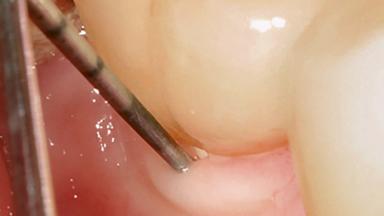

Treatment of Peri-Implant Mucositis at a Zirconia Implant

Frank Schwarz, Ausra Ramanauskaite

Recent clinical studies, most with short-to-medium term observation periods, have reported on the favorable clinical performance of zirconia implants in terms of survival rates, clinical, and radiographic outcomes (Roehling and coworkers 2016; Roehling and coworkers 2017; Rodriguez and coworkers 2018; Lorenz and coworkers 2019). Nonetheless, a rather high incidence of peri-implant disease at zirconia implants (39% of implants) was noted throughout a two-year period, highlighting the need for treatment protocols of peri-implant diseases at zirconia implants (Becker and coworkers 2017).